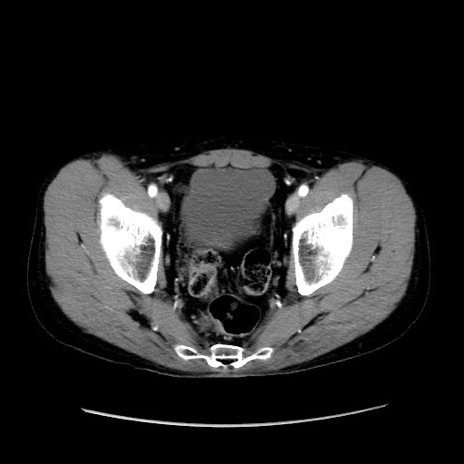

症例37(横断像)

【症例】40歳代 男性

【主訴】腹痛

【現病歴】4時間ほど前に電車に乗車中に臍部上より腹痛出現。徐々に増悪し起立困難となり、救急外来受診。生ものは数日食べていない。今朝お雑煮を食べた。

【身体所見】BT 36.8℃、BP 117/84mmHg、HR 91/min、SpO2 97%、苦悶様、腹部:臍上部広範囲圧痛あり、反跳痛±

【データ】WBC 8100、CRP 0.03